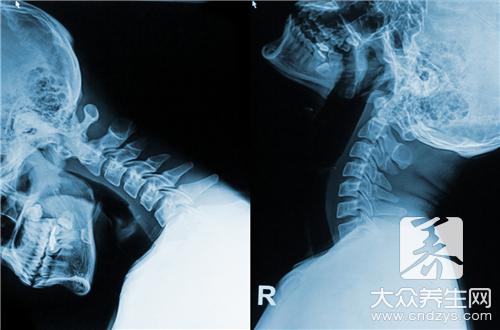

颈椎病治疗偏方

颈椎病几乎是每一个人都有的,这和现在的生活方式有很大的关系,特别是一些办公室的人,每天都会坐很长时间,时间长了就会对颈椎造成很大的影响,颈椎病就不稀奇了,患上了颈椎病会有很多不适的症状,特别是天冷的时候疼痛的症状会很明显,了解颈椎病治疗偏方很有用。